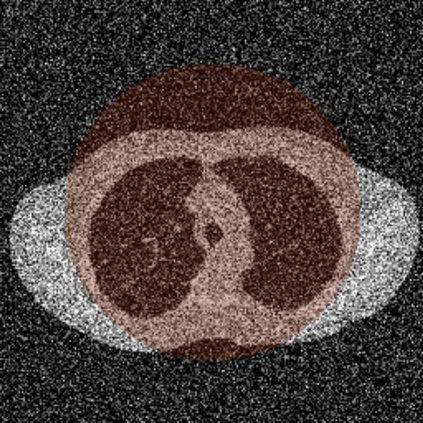

Anatomically consistent field-of-view (FOV) completion to recover truncated body sections has important applications in quantitative analyses of computed tomography (CT) with limited FOV. Existing solution based on conditional generative models relies on the fidelity of synthetic truncation patterns at training phase, which poses limitations for the generalizability of the method to potential unknown types of truncation. In this study, we evaluate a zero-shot method based on a pretrained unconditional generative diffusion prior, where truncation pattern with arbitrary forms can be specified at inference phase. In evaluation on simulated chest CT slices with synthetic FOV truncation, the method is capable of recovering anatomically consistent body sections and subcutaneous adipose tissue measurement error caused by FOV truncation. However, the correction accuracy is inferior to the conditionally trained counterpart.